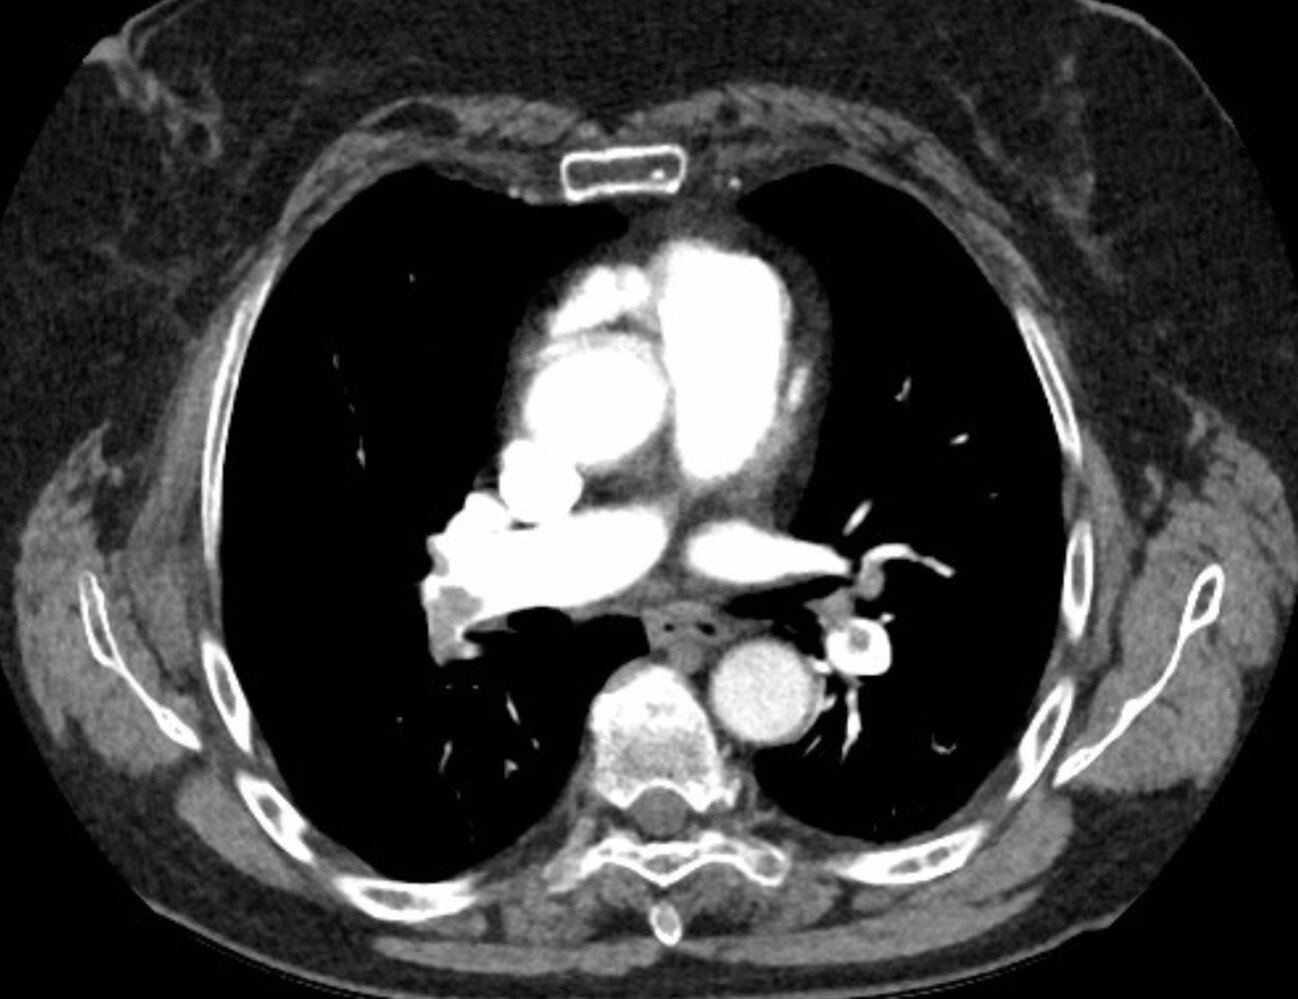

Chest imaging [20]

• Goal: to evaluate for underlying cardiopulmonary comorbidities or etiologies

• CXR: e.g., CXR findings of AHF, CXR findings of pneumonia, CXR findings of COPD

• CT pulmonary angiography: See β€œFindings” in β€œCTPA.”